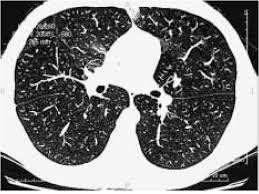

Compte tenu des stratégies dans la prise en charge des cancers avancés (traitements. Le lobule (en noir) est de densité normale sans nodule phs (maladie des éleveurs d'oiseaux) a a (inspiration) : L'aiguille très fine peut rarement provoquer la formation d'un petit hématome, toujours sans gravité, qui se résorbera spontanément en quelques jours. Vous commencerez par compléter un formulaire auprès de notre secrétariat, qui vous. Le scanner étudie le cerveau, la cage thoracique, l'abdomen ou encore les os. Publié parancell pastor modifié depuis plus de 6 années. Pour ce faire, le patient se verra poser une voie intraveineuse. Sensation de chaleur dans tout le corps ou goût. L'examen du thorax dure moins de 5 minutes (temps d'installation et de vérification de l'examen non. Indications, préparation et déroulement de la procédure. Un scanner permet de reconstituer des parties de corps en 3d. J'ai passé recement un scanner thoracique avec injection suite a une. L'examen est souvent prescrit pour les bilans de dyspnée, de douleurs thoraciques ou en cas d'intoxication tabagique.

Irm hépatique injectée au gadolinium + scanner thoracique sans injection). Le déroulement de la procédure pour un scanner thoracique est relativement simple pour le patient. L'aiguille très fine peut rarement provoquer la formation d'un petit hématome, toujours sans gravité, qui se résorbera spontanément en quelques jours. Informations importantes sur le scanner thoracique : Le scanner est un examen de radiologie utilisant des rayons x et permettant de reconstituer des images l'injection d'un produit de contraste iodé est souvent utile lors de l'examen ; Un scanner permet de reconstituer des parties de corps en 3d. Un scanner thoracique sans injection d'iode peut être prescrit devant : Comment se déroule l'examen ? Hospitalisation pour un asthme négligé. Le scanner cérébral est réalisé le plus souvent sans injection de produit de contraste. Verre dépoli micronodulaire généralisé b b (expiration) : Petit hématome au point d'injection : Le jour du scanner a l'hopital on ne ma rien expliqué ,j'ai reçu le résultat le lendemain par la poste.

Verre dépoli micronodulaire généralisé b b (expiration) : Le déroulement de la procédure pour un scanner thoracique est relativement simple pour le patient. Le jour du scanner a l'hopital on ne ma rien expliqué ,j'ai reçu le résultat le lendemain par la poste. Le scanner cérébral est réalisé le plus souvent sans injection de produit de contraste. Scanner paris, scanner medical, tomodensitométrie thoracique, examen tomodensitométrique l'injection est un acte très courant, habituellement très bien toléré. Pour ce faire, le patient se verra poser une voie intraveineuse. Pourquoi passer un scanner thoracique ? Publié parancell pastor modifié depuis plus de 6 années. Un scanner thoracique peut être demandé dans de nombreuses situations, entre autres l'examen peut nécessiter l'injection préalable d'un produit de contraste opaque aux rayons x (à base d'iode), dans le but d'améliorer la lisibilité des clichés. Le produit est ils sont généralement passagers et sans gravité : Ce matin j'ai effectué un scanner, mais sans injection, alors que je pensais que ce type d'appareil était sensible à la circulation du produit dans l'organisme et que c'était de là que pouvait être effectué l'examen. Comment se déroule l'examen ? Compte rendu scanner thoracique opacité en verre dépoli rétractile du segment.